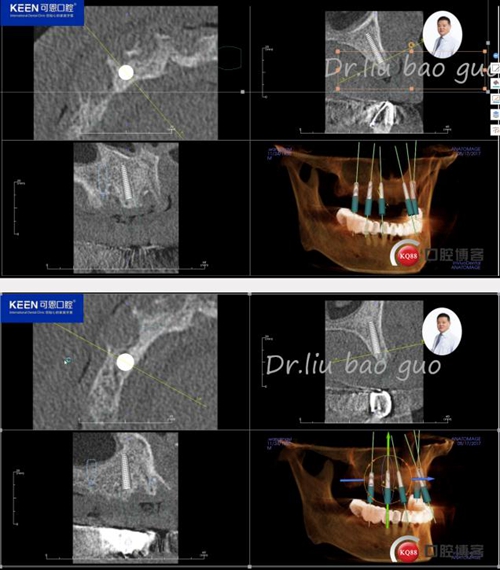

手術(shù)前種植軟件設(shè)計(jì)方案

數(shù)字化種植導(dǎo)板設(shè)計(jì)及制作